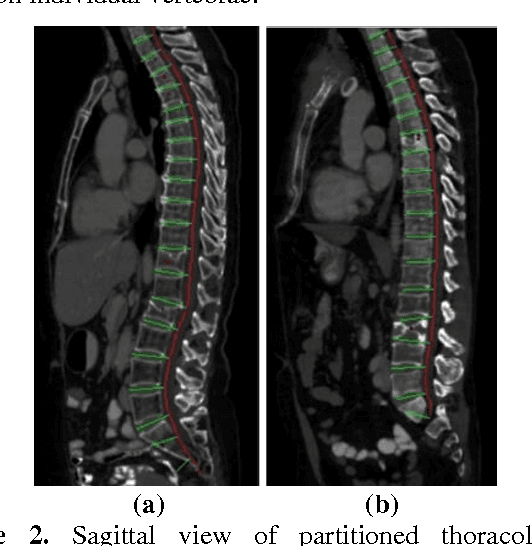

Classification of vertebral compression fractures (VCF) having osteoporotic or neoplastic origin is fundamental to the planning of treatment. We developed a fracture classification system by acquiring quantitative morphologic and bone density determinants of fracture progression through the use of automated measurements from longitudinal studies. A total of 250 CT studies were acquired for the task, each having previously identified VCFs with osteoporosis or neoplasm. Thirty-six features or each identified VCF were computed and classified using a committee of support vector machines. Ten-fold cross validation on 695 identified fractured vertebrae showed classification accuracies of 0.812, 0.665, and 0.820 for the measured, longitudinal, and combined feature sets respectively.